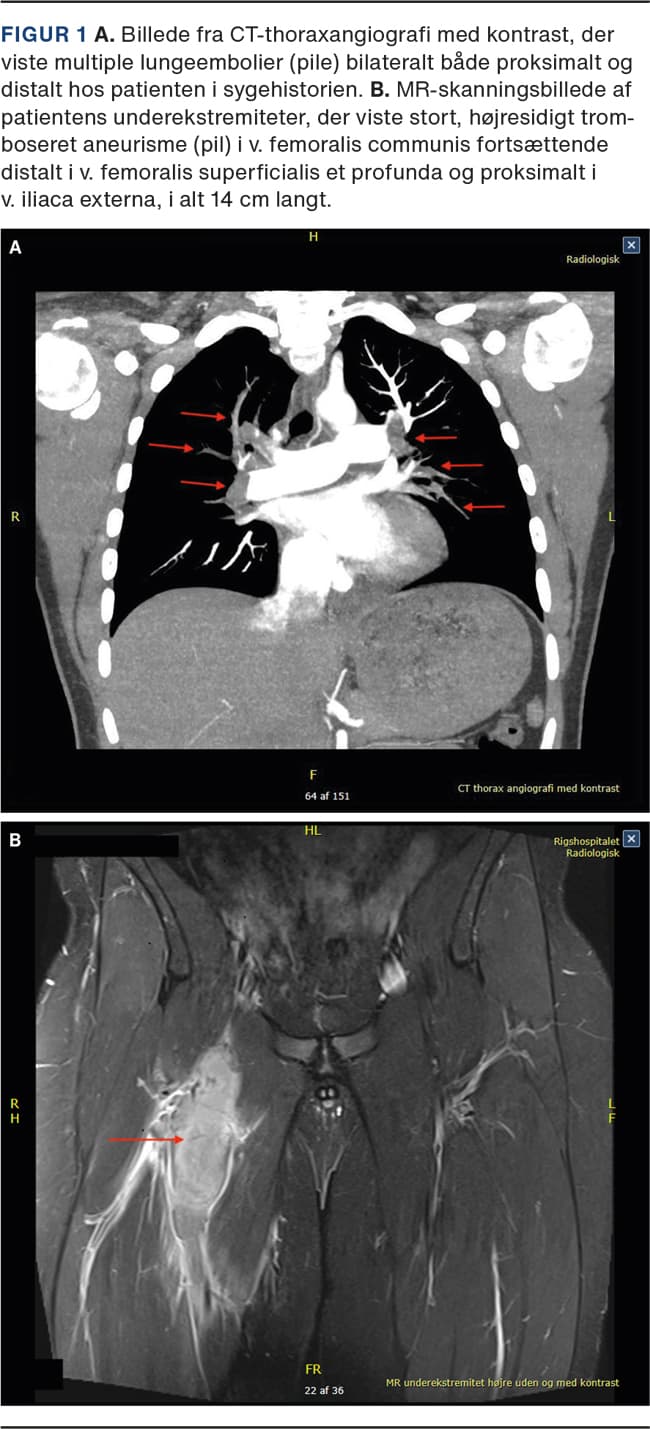

På baggrund af anamnesen og de kliniske fund havde man mistanke om LE. Koncentrationen af fibrin D-dimer var 8,7 mg/l. Torakal CT-angiografi viste multiple LE bilateralt med affektion af samtlige lungelapper (Figur 1A). En transtorakal ekkokardiografi (TTE) viste tegn på øget tryk i lungekredsløbet. Patienten blev overflyttet til en intensivafdeling til observation og sat i behandling med lavmolekylært heparin (tinzaparin 175 IE/kg).

Ultralydskanning af højre underekstremitet, udført på mistanke om dyb venetrombose (DVT), viste en trombe på 4 cm i diameter i v. femoralis communis fortsættende distalt i v. femoralis superficialis et profunda og proksimalt i v. iliaca externa. For at udelukke paraneoplastisk sygdom udførte man en MR-skanning af underekstremiteterne, som viste et 14 cm langt, højresidigt aneurisme i v. femoralis communis med massiv trombedannelse (Figur 1B).